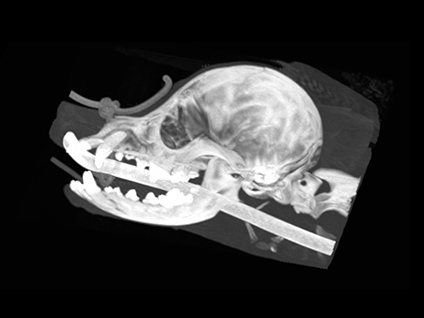

整形外科におけるCT検査

骨折時の状態を立体的に把握し、術前情報を提供できます。 先天性の骨の変形や骨折後の不正確な癒合などの変形を、3Dプリンターを併用することで骨模型を作成し、手術前に整復計画を正確に行うことができます。 成長期における骨格異常や関節の不一致を、より早期に発見して対応すること事ができます。